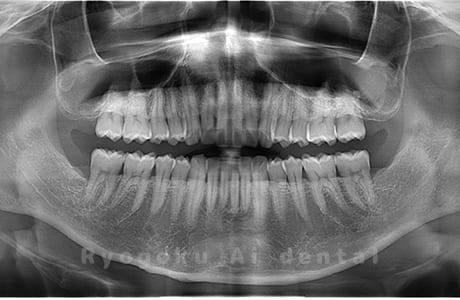

真っ直ぐ生えている親知らず

親知らずが真っ直ぐ生えているタイプです。

このタイプは真っ直ぐ生えていて咬み合わせに問題がなければ、抜歯しないケースもあります。ただし、虫歯になっていたり、痛みがあったり、咬み合わせが悪かったりすると抜歯をおすすめします。